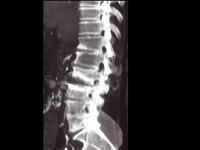

问题 男,65岁,腰背部疼痛1月余,结合图像,最可能的诊断是?(?)

选项 A.脊椎结核 B.椎体压缩骨折 C.脊椎退行性变 D.脊椎转移瘤 E.L2~L3椎间盘炎

答案 E